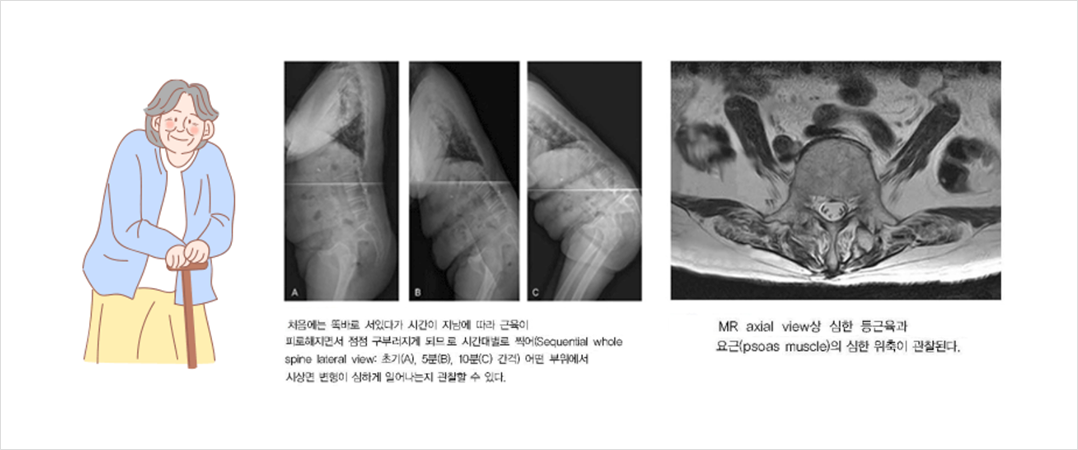

또한 처 음에는 똑바로 서 있다가 시간이 지남에 따라 근육이 피로해지면서 시간대별로 찍어(초기, 5분, 10분 간격) 어떤 부위에서 시상면 변형이 심하게 일어나는지 관찰할 수 있습니다. 최근에는 저선량 체중부하 X ray 검사인 EOS 검사를 이용하기도 합니다.

자기공명영상(MRI)를 촬영하여 척추협착증이나 추간판탈출증에 대한 진단과 요근과 척추주변근육의 심한 위축을 확인하게 됩니다.